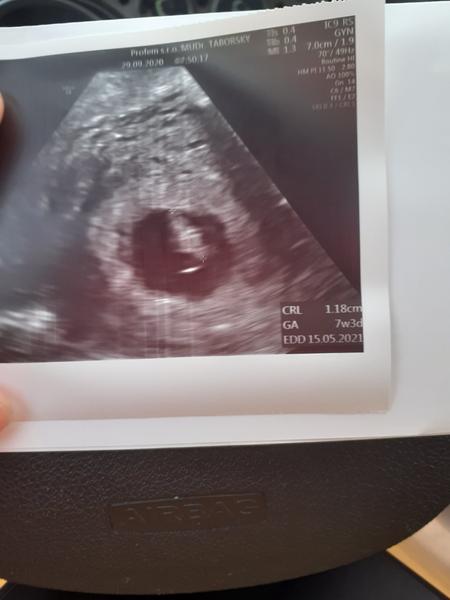

Ahojte . Som po IVF, prosím viete mi povedať že či by to mohol byť plod alebo nie? Doki sa vyjadril že je to ešte malé, ja som bola nejak tak v šoku že som sa ani nepýtala.... Teraz idem v stredu až ale mám pocit že vo mne nič nie je :/ žiadne príznaky, akurát sem tam bolest ako na menzes ,a zdalo sa mi se som mala dnes pri utreti trošku hnedý hlien ..som v čase ms .. veľmi sa bojím. Mám za sebou 6 neúspešných IVF... tento vklad bol s darovanym embryom v Brne . Ďakujem za každú radu ❤

@kelerub chcela by som ťa nasledovat🙂 . Prajem veľa zdravicka aj tebe aj malej/mu 🍀 Idem zajtra ráno, preto som taká vystresovana už čítala som veľa o zamklom potrate, raz som mala biochemicke tak uvidíme. Hcg na 13dpt som mala 443 a o dva týždne 19403 .. Teraz prešiel týždeň tak už jak sa blíži sono sa obávam. Ja som streser až som otravna...